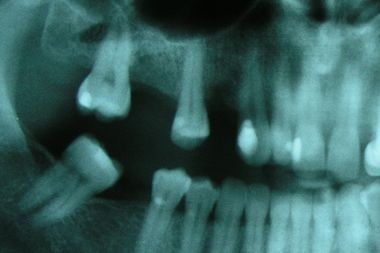

В таких случаях возможны два варианта протезирования: - с помощью различных конструкций съемных протезов или с помощью дентальной имплантации. Пациентка выбрала второй вариант. После рентгенологического обследования и согласования стоимости лечения были установлены два винтовых имплантата Astra Tech в область 16 и 14 зубов.

Если бы выбрали обычный метод протезирования (правда, протезирование на имплантатах стало уже обычным делом), то пришлось бы обточить три здоровых зуба и изготовить металлокерамический мост из пяти единиц. На нижней челюсти сложившаяся ситуация будет исправлена с помощью покрытия металлокерамической коронкой последнего моляра и установки винтового имплантата на место отсутствующего нижнего правого большого коренного зуба.